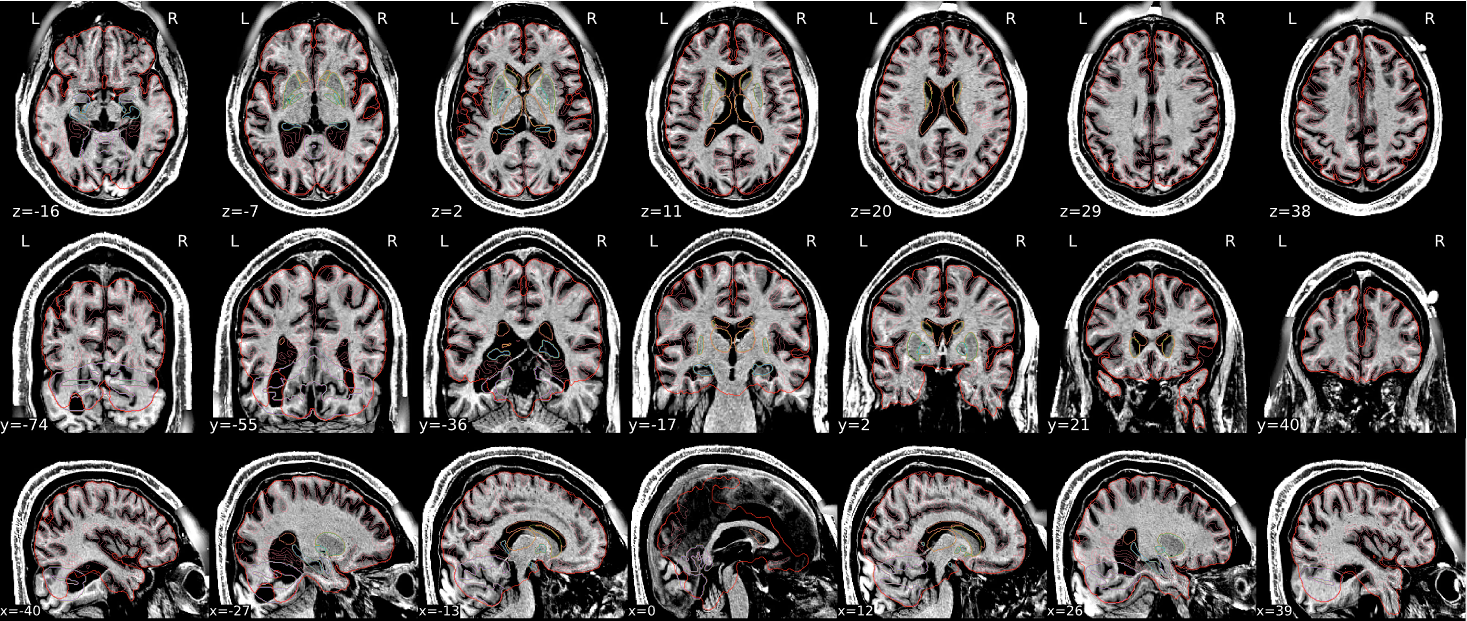

EPI spatial normalisation

This QC step shows the registration of the EPI image to MNI space.

Example of a good subject

- If the registration performed well, you should see an overlap (i.e., correspondence of structures) between the MNI template and the EPI registered to the MNI space.

- If parts of the brain are missing due to the scanner field of view, this is fine. For example, the cerebellum may be cut off for a participant with a large head.

Example of a bad subject

- In case of poor registration, you should see a misalignment of the EPI and the MNI template

Summary

| good | bad |

|---|---|

| Overlap (i.e. match of structures) between the MNI template and the EPI registered in the MNI space | Misalignment of the EPI and the MNI template |

| If parts of the brain are missing because the field of view of the scanner is limited, the EPI spatial normalisation does not have to be excluded e.g. cerebellum cut off in person with large head |

If parts of the brain are missing because the field of view of the scanner is limited, the EPI spatial normalisation does not have to be excluded (e.g. cerebellum cut off in person with large head)